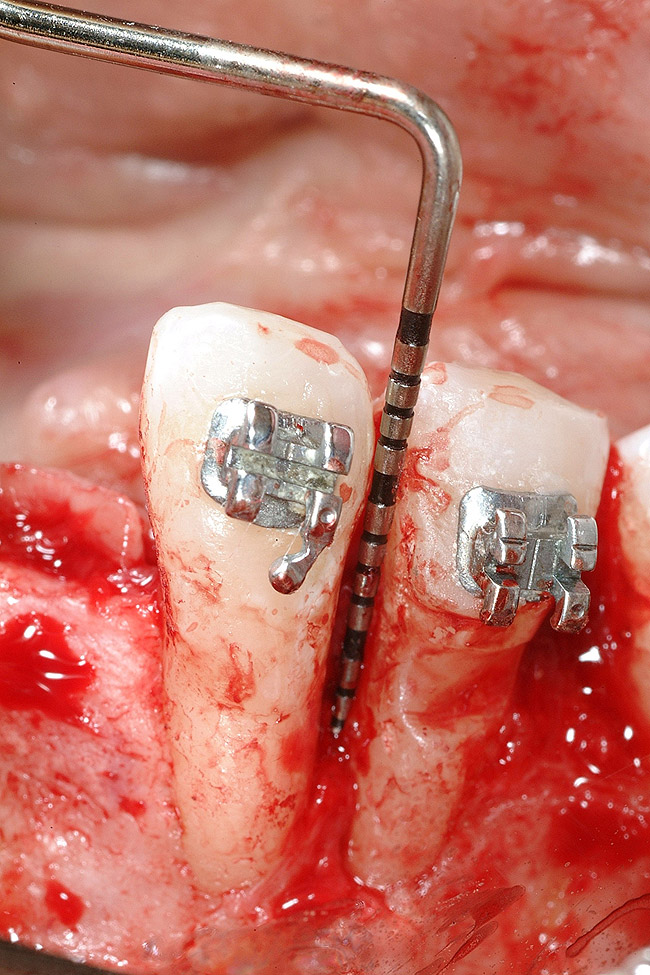

The patient had no medical concerns and had a history of an implant placement in December 2002 when she was 25 years old. In February 2005, she presented with a mobile implant and an associated advanced peri-implantitis. Radiographic review at the initial examination demonstrated significant destruction of the dentoalveolar ridge around the implant as well as around the adjacent natural dentition. Emergency-based treatment involved surgical implant removal only and debridement of the infection (Figure 4 and Figure 5). Following uneventful healing, an advanced ridge defect was apparent at the edentulous site and moderate and advanced attachment loss noted at No. 22D and No. 21M, respectively (Figure 6 and Figure 7). This case demonstrates bone loss of two separate origins: lack of bone because of tooth agenesis and destruction of bone from inflammatory peri-implantitis.

Figure 4  Vertical ridge defect in site No. 22.

Figure 4

Figure 5  Horizontal ridge defect in site No. 22.

Figure 5